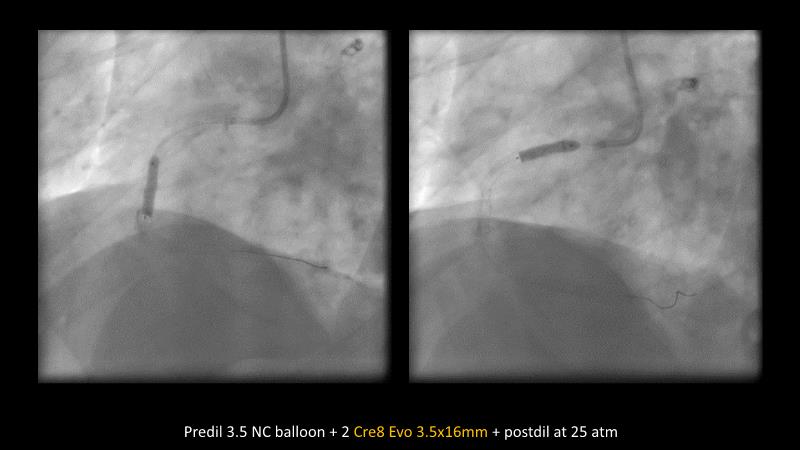

Making treatment and management of complex PCIs easier with Cre8 EVO

Maximize patient clinical outcomes in complex percutaneous coronary interventions (PCIs) by joining this session. Discover how accurate patient evaluation, advanced imaging/functional modalities, optimized procedures, and the Cre8 EVO device contribute to improved safety and efficacy, and review the challenges associated with DES implantation in complex PCIs.

- To understand how the Cre8 EVO unique technology and its specific design may contribute to improve the procedural success and clinical outcome of complex PCIs in complex patients